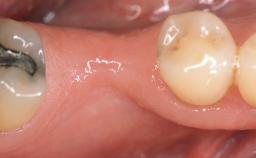

A 30-year-old woman was referred by her general dentist for evaluation of an esthetic complication related to previous implant treatment for congenitally missing maxillary lateral incisors. The patient’s chief complaint was the inadequate esthetic appearance of her smile. The case demonstrates the use of a combined approach to achieve optimal results. Two different flap designs - a tunnel technique and a coronally advanced flap - are employed based on the surgical objectives for the affected site.

Prosthesis Type FDP

Soft Tissue Grafting Yes